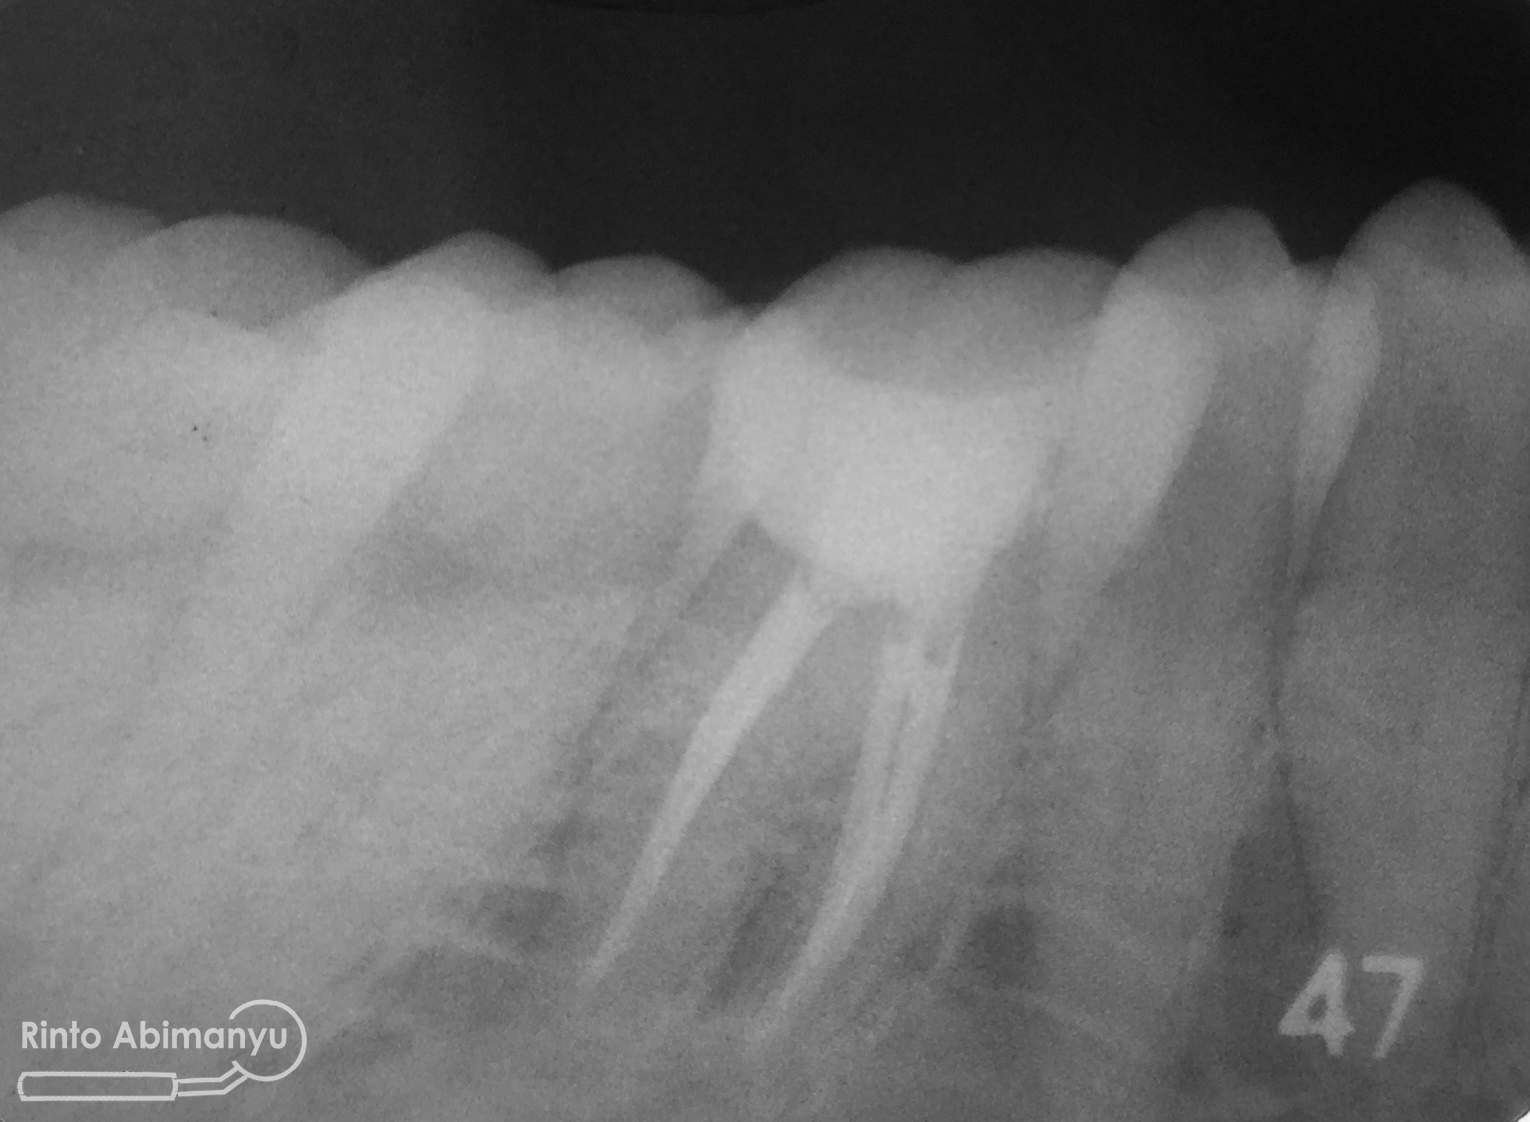

Kemudian dilakukan foto ronsen gigi tersebut…

Terlihat kavitas sudah mengenai kamar pulpa, dan dari hasil tes respon dingin serta tes perkusi menunjukkan hasil negatif… Kondisi yang saya temukan diinfokan ke pasien dan dijelaskan rencana perawatan untuk giginya, setelah pasien mengerti dan menyatakan setuju perawatan baru dimulai…